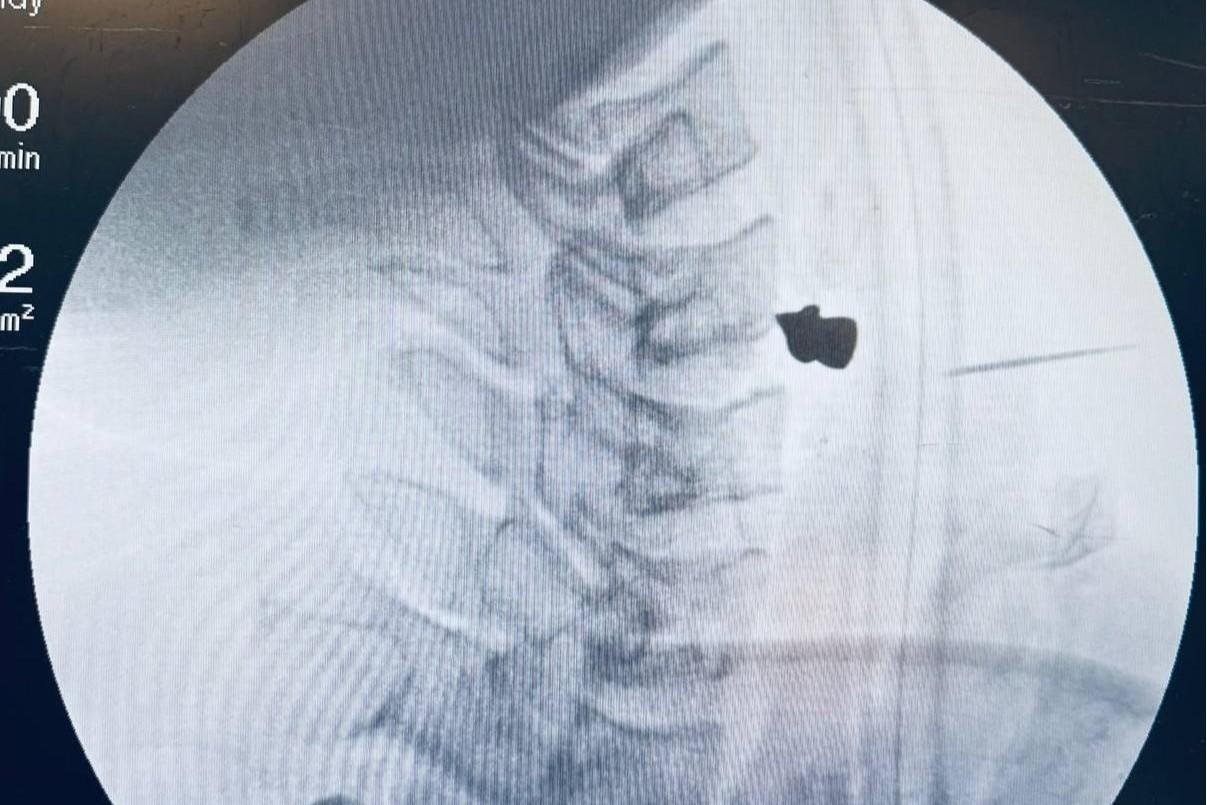

Казанские врачи достали пулю из шеи пациента, чудом не задевшую артериюПарень случайно выстрелил в себя